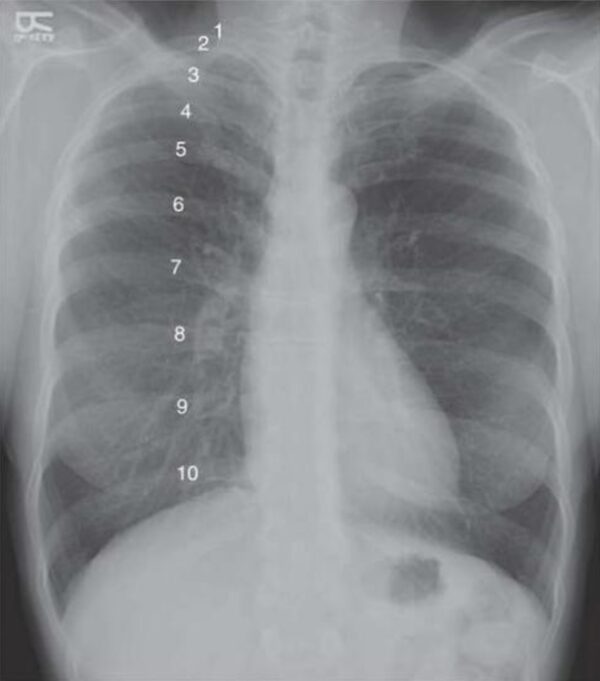

Edema y derrames

Los trastornos que afectan la función cardiovascular, renal o hepática suelen manifestarse con la acumulación anormal de líquido en los tejidos, fenómeno conocido como edema, o en las cavidades corporales,…